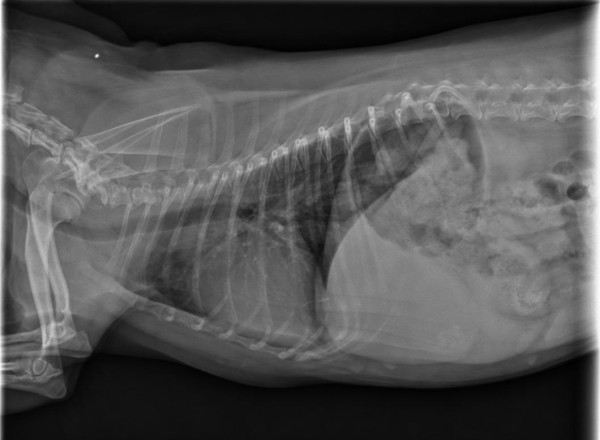

La radiographie vétérinaire repose sur l’utilisation des rayons X pour obtenir une image du corps et des différents organes de votre animal, qu’il s’agisse d’un chien, d’un chat ou d’un nouvel animal de compagnie (NAC). Il s’agit d’un examen en médecine vétérinaire qui constitue un outil essentiel au diagnostic de santé et à la prise en charge de votre animal de compagnie.

En radiographie, les tissus apparaissent en nuance de gris, du noir au blanc : on peut y voir les graisses, les tissus mous, les structures minéralisées (dont les os), et le métal.

-La radiographie thoracique : en cas de toux, essoufflement, difficultés respiratoires afin de rechercher des lésions médiastinales, pleurales, pulmonaires, ou encore cardiaques

Il est enfin incontournable lors de la prise en charge initiale des animaux traumatisés, après une chute ou un accident (recherche de fractures, d’épanchement, de lésions thoraciques).